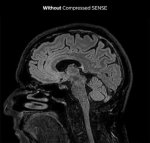

На МРТ мозг одинаковый. Это нажбровные дуги крупнее только и всего.